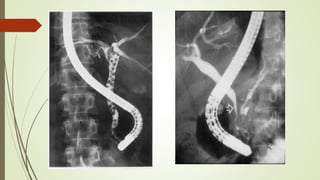

Endoscopic Retrograde Cholangiopancreaticography (ERCP)

• Permits direct visualization of biliary tract

• Highly accurate in the diagnosis of biliary obstructions

• Simultaneous therapeutic interventions like sphincterotomy,

stricture dilatation & stent placement can be done

• Acquisition of tissue for biopsy & brushings for cytology

Advantages

• Invasive

• Requires sedation

• Cannot be performed if altered anatomy precludes

endoscopic access to ampulla (e.g., Roux-en-Y loop);

• Has complications (e.g., pancreatitis)

Disadvantages

Percutaneous Transhepatic Cholangiography (PTC)

 Requires the passage of a needle through the skin and subcutaneous tissues into the hepatic

parenchyma and advancement into a peripheral bile duct

 When bile aspirated, a catheter is introduced through the needle, and radiopaque contrast

medium is injected

 Applicable for lesions proximal to CHD

• Direct imaging of bile ducts

• Simultaneous therapeutic intervention

• Difficult with non dilated intra hepatic bile ducts

Disadvantage